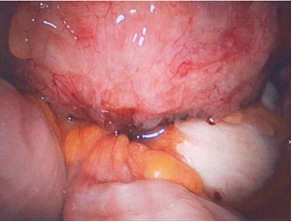

Các trường hợp có nghi ngờ lạc tuyến trong cơ tử cung trên nội soi đều được siêu âm màu và chụp cộng hưởng từ nhân để khẳng định chẩn đoán bởi các bác sĩ khoa chẩn đoán hình ảnh bệnh viện ĐHYD đảm nhận.

Nội soi buồng tử cung có nốt lạc tuyến |

Nội soi ổ bụng và mô học Adenomyosis |